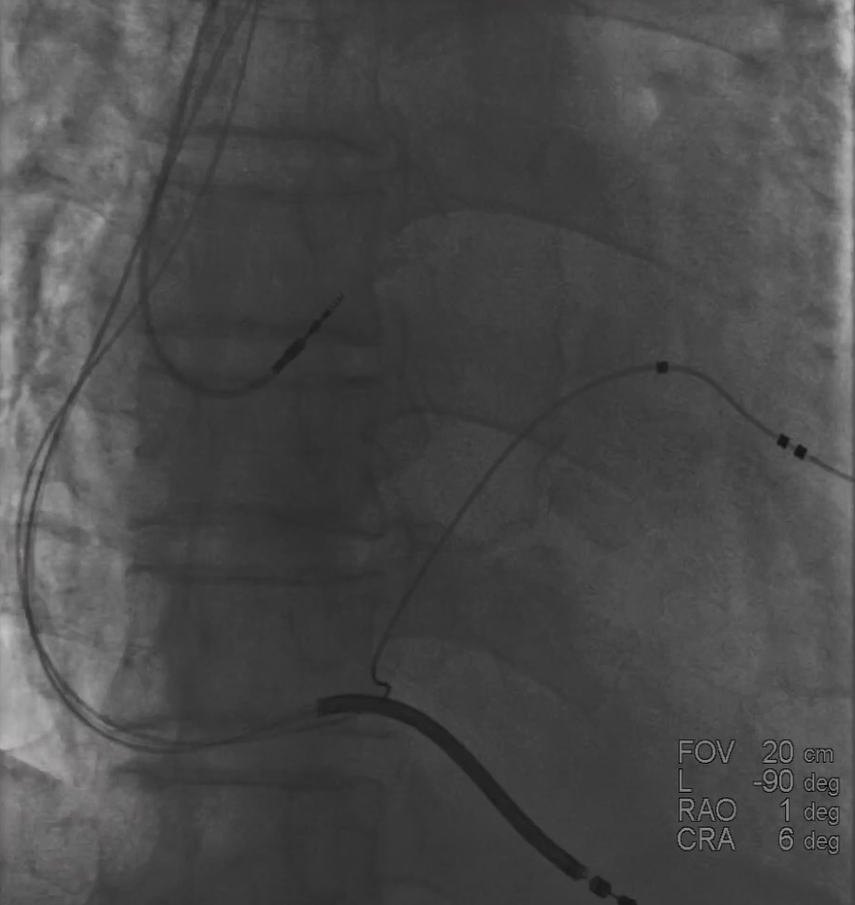

确定开口位置之后,发现CS开口朝下,首先尝试利用AL1+泥鳅导丝寻找冠状窦,反复几次均无法进入,更换AL2+泥鳅成功进入冠状窦。

图四 AL2+泥鳅进入冠状窦

3.静脉狭窄、近端有瓣,电极如何进入?

鞘管进入窦口之后冒烟显示静脉有部分狭窄,球囊造影的时候也出现阻力,造影显示近端有瓣,无法通过电极,最终利用球囊扩张,让电极顺利通过静脉瓣。

图五&六 造影发现有静脉瓣

图七 预扩球囊扩张血管